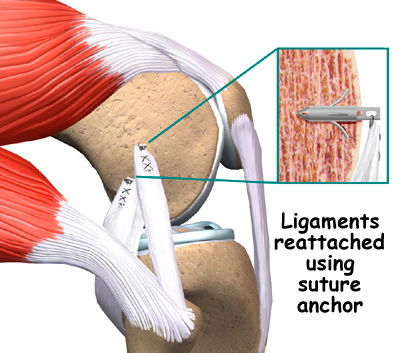

If medical treatments are not satisfactory, ligament repair surgery may be an effective treatment.

The repair work can be done in 1 of 2 ways: Tendon from another area may be. An mcl graft can be.

The first choice for professional athletes worldwide. American technology, made in usa. The ligament is attached to the bone to secure it.